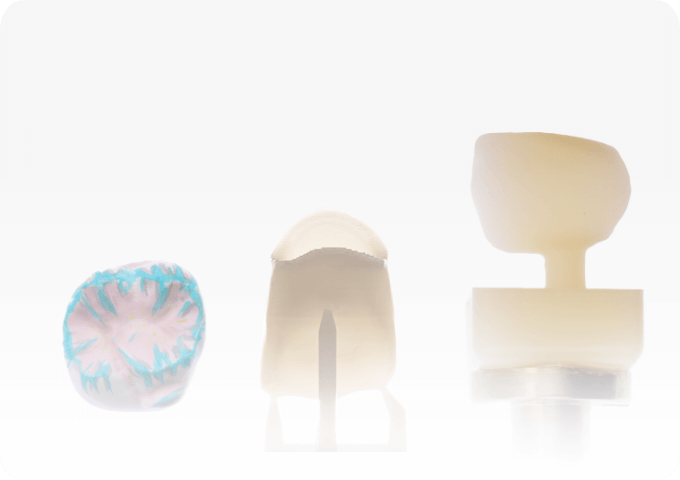

Singular design

Diagnostic interdisciplinary planning

Crown Lengthening Guide

Recontouring soft tissue levels

Anterior Platform

Predictable deprogramming

Digital Restorations

Designed preserving the biometry

Analog Restorations

Printed, ceramics or zirconia

Abutment design

Transmucosal options

Services are optional, on-demand, and fully managed by third-party providers

Access Digital Services

Directly from Your Smilecloud Case

Connect with Metalab. Without leaving your workflow.

Smilecloud includes access to independent digital service providers for design and manufacturing. Submit requests directly from your case, while staying fully in control.